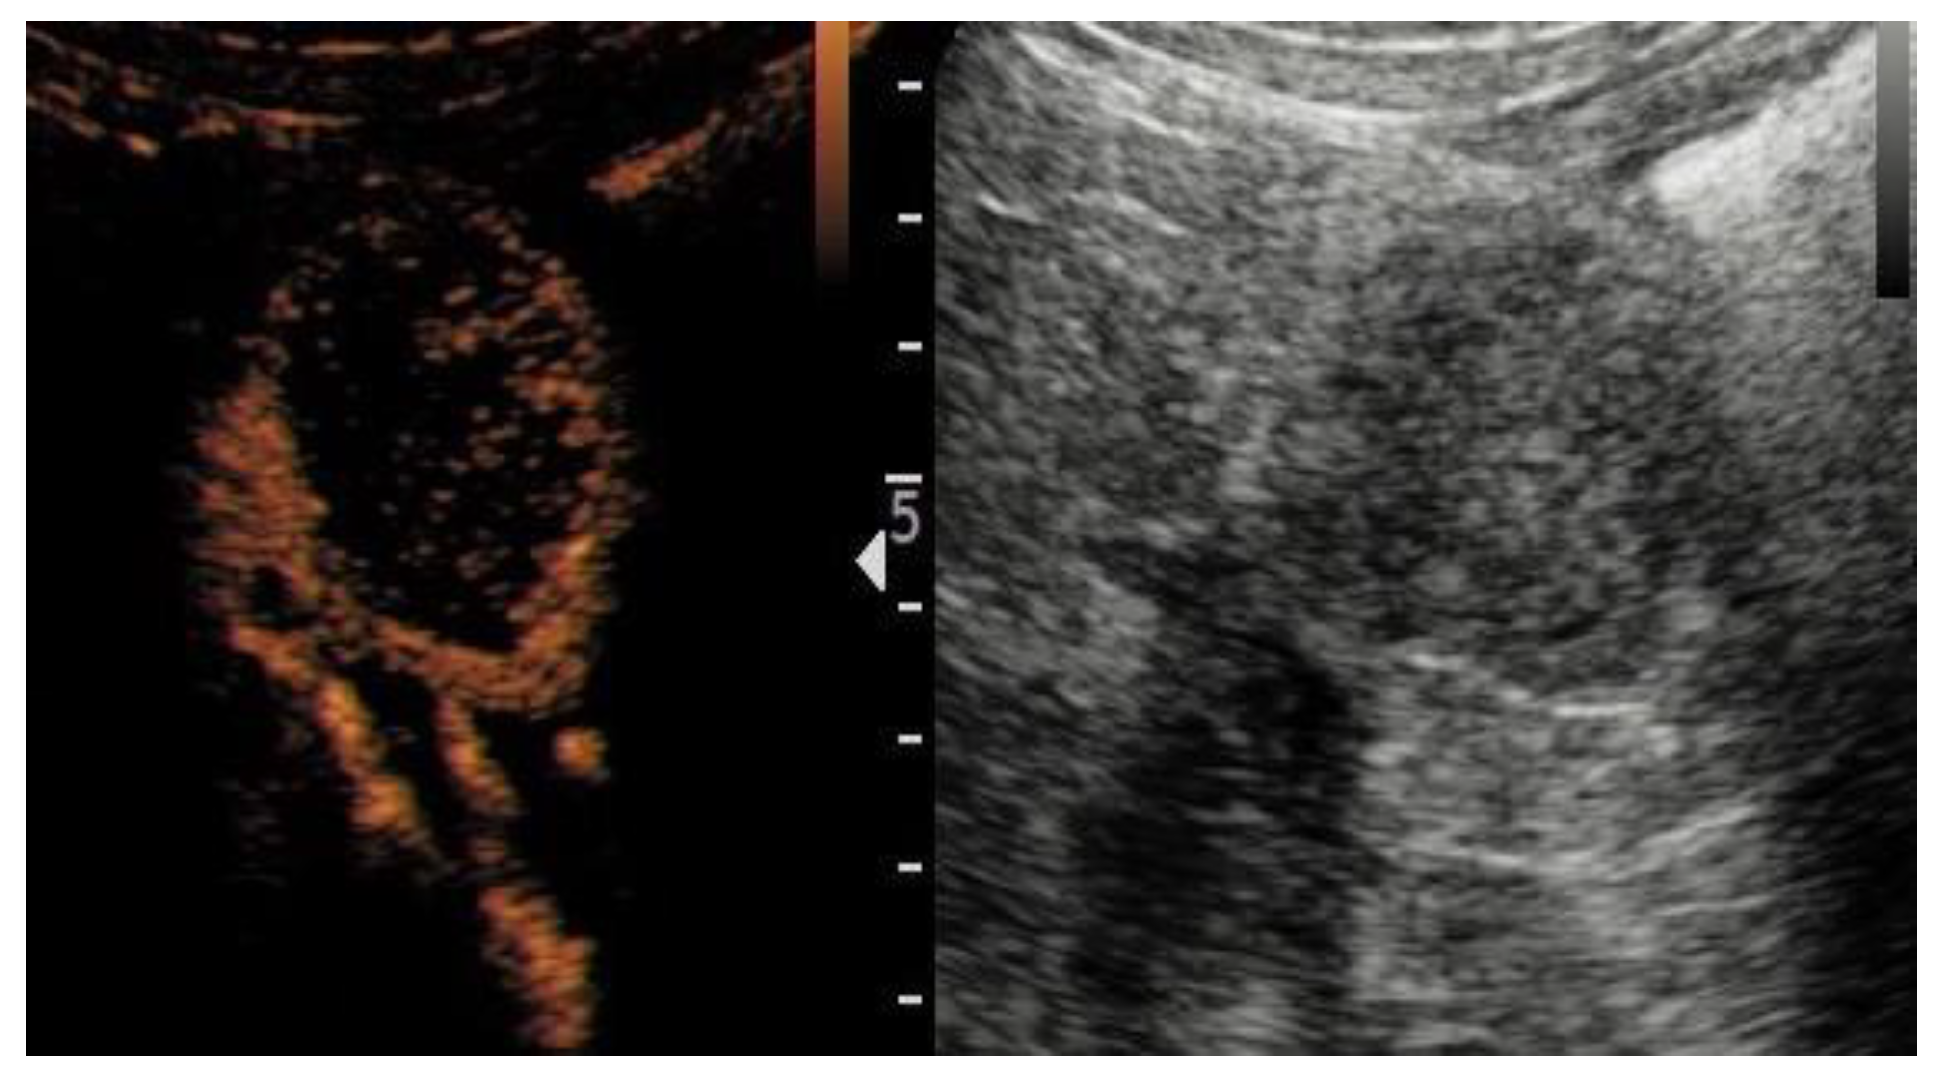

| Wash-in | ||||

| Fast | 95 (75.4%) | 83 (80.6%) | 12 (52.2%) | 0.004 |

| Synchronous/Slow | 31 (24.6%) | 20 (19.4%) | 11 (47.8%) | |

| Enhancement | ||||

| Homogeneous | 48 (38.1%) | 27 (26.2%) | 21 (91.3%) | <0.001 |

| Heterogeneous | 78 (61.9%) | 76 (73.8%) | 2 (8.7%) | |

| Wash-out | ||||

| Fast | 55 (43.7%) | 52 (50.5%) | 3 (13.0%) | 0.001 |

| Synchronous/Slow | 71 (56.3%) | 51 (49.5%) | 20 (87.0%) | |

| Rim-like enhancement | ||||

| No | 30 (23.8%) | 15 (14.6%) | 15 (65.2%) | |

| Yes | 96 (76.2%) | 88 (85.4%) | 8 (34.8%) | <0.001 |